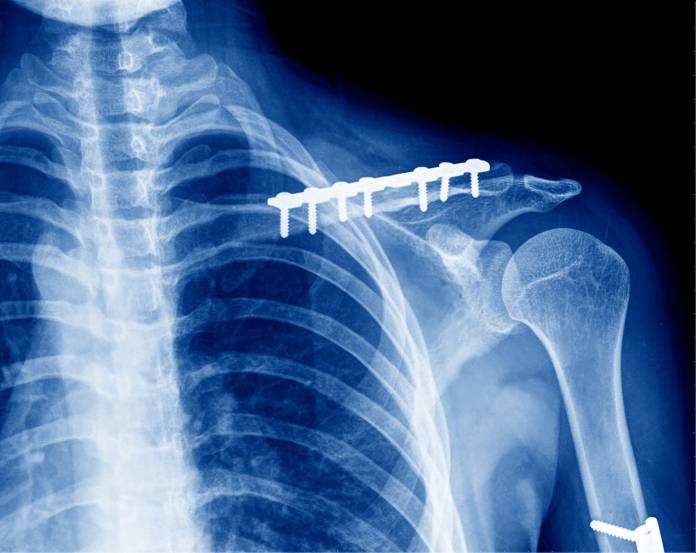

Eine Operation am Schlüsselbeinbruch wird häufig mit einem offenen (langen) Schnitt vorgenommen, kann zum Teil aber auch durch kleine Zugänge (minimal-invasiv) geschehen. Eine Vollnarkose ist für diesen Eingriff erforderlich. Die Knochenfragmente werden in die richtige Lage gebracht. Dann werden sie mit Fremdmaterial aneinander befestigt. Zur Versorgung kommen entweder Platten und Schrauben oder manchmal Drähte in Frage. Heutzutage ist es auch möglich, einen Längsnagel (Prevot-Nagel) in den Knochen zu schieben und somit die Bruchanteile zusammenzuhalten. Nach der Fixierung des Knochenbruches wird die Hautwunde vernäht. Die Schrauben, Platten, Nägel oder Drähte können nach längerer Zeit in einer Zweitoperation wieder entfernt werden, oft werden sie aber im Körper belassen.